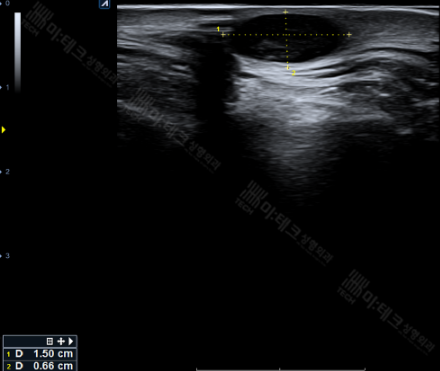

부산표피낭종은 다음과 같이 표면에, 경계가 명확하게,

뒤쪽으로 그림자가 확실하게 잡히는 까만 음영으로 보이게 됩니다.

경계가 명확한, 주머니에 깨끗하게 둘러싸인 부산표피낭종의 경우 핀홀법 수술이 가능합니다.